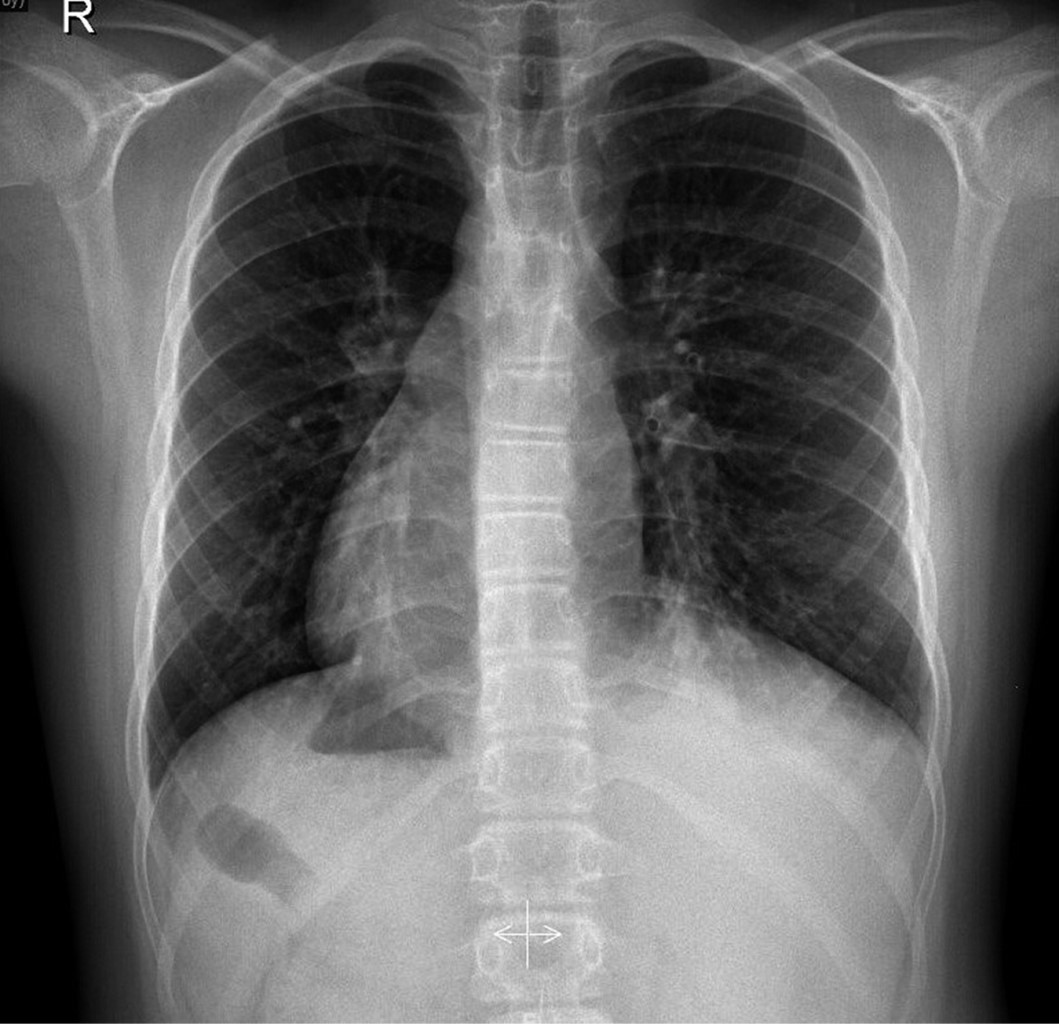

Se realiza analítica sanguínea, proteína C reactiva 94 mg/L, procalcitonina 0.46 ng/mL, Hb 11.7 g/dL, hematocrito 35.6%, leucocitos 20,100, neutrófilos 17,400 (86.4%). Hemocultivo negativo a los cinco días de incubación. Serología negativa para virus respiratorios, incluido micoplasma. Radiografía de tórax (Figura 1) en la que se observa consolidación en lóbulo inferior izquierdo, y opacidades tubulares en esa misma localización, que podrían corresponder con bronquiectasias en paciente con dextrocardia e inversión de vísceras abdominales; este hallazgo junto con las infecciones respiratorias de repetición hicieron sospechar de un síndrome de Kartagener, por lo que se amplía el estudio con tomografía axial computarizada de alta resolución (TACAR) torácica (Figura 2), descartando la existencia de bronquiectasias.

Tras realizar TACAR se descarta Kartagener, porque no cumple tríada del síndrome (bronquiectasias + sinusitis paranasal + SIT). No obstante, ante las tres neumonías, solicitamos estudio genético para determinar la presencia de patrones genéticos descritos para discinesia ciliar primaria así como estudio confirmatorio en células epiteliales nasales o bronquiales mediante la observación de cambios ultraestructurales por microscopía electrónica. Sin embargo, el paciente regresó a su país de origen, por lo que no se pudo completar su evaluación.

Figura 2